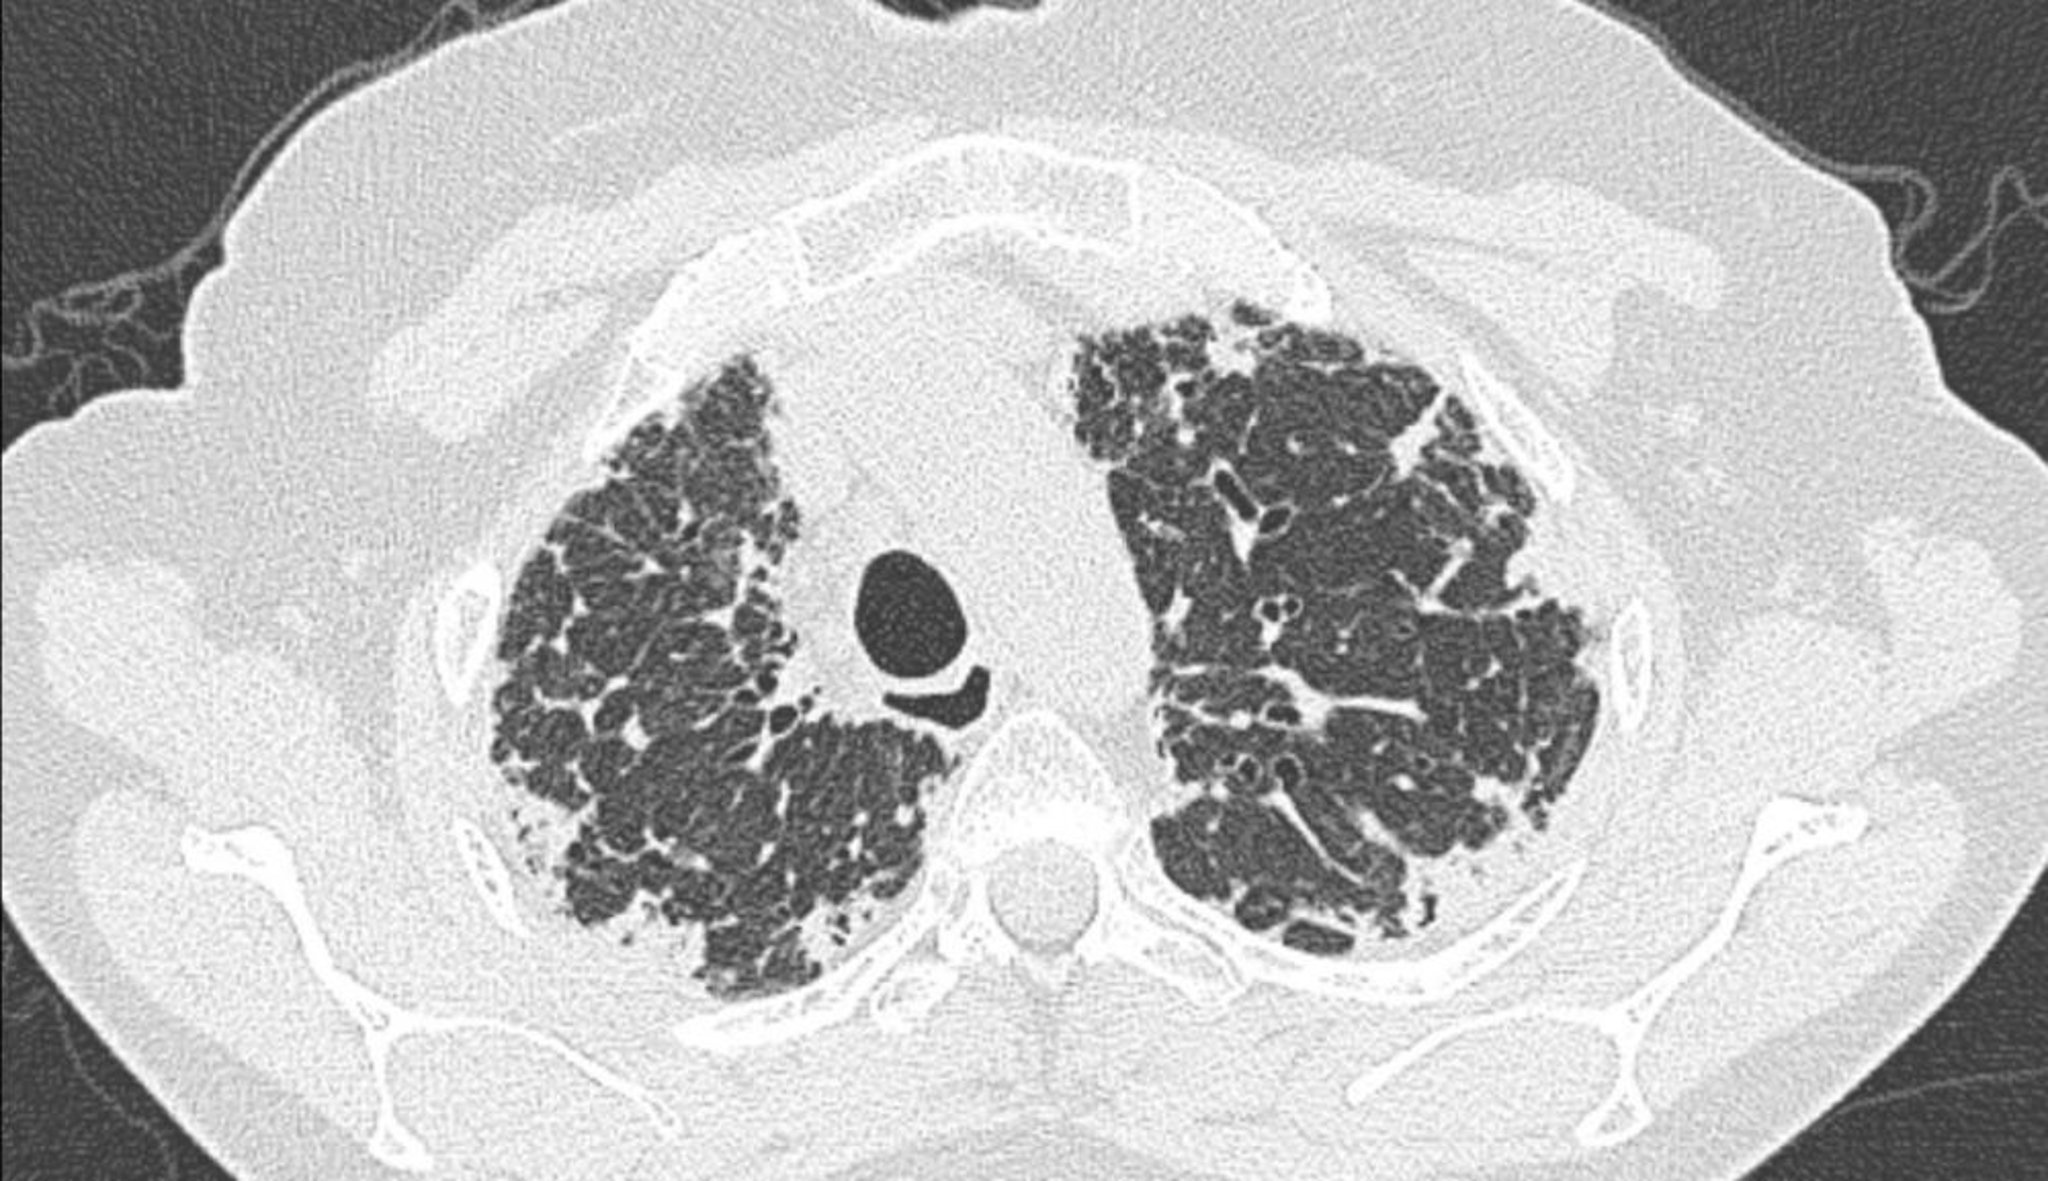

Fibroélastose pleuroparenchymateuse idiopathique (TDM)

La TDM du thorax montre un épaississement pleural et sous-pleural.

Image courtoisie de Joyce S. Lee, MD, MAS.